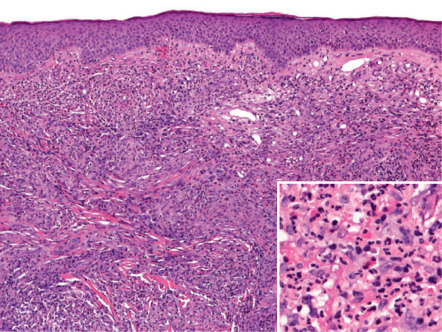

Pathology

In the dermis, there are perivascular and interstitial infiltrates of neutrophils, lymphocytes and plasma cells, admixed with numerous eosinophils. Characteristically, the inflammation spares the upper papillary dermis, creating a “grenz zone” ( Fig. 25.4 ). Features of leukocytoclastic vasculitis are most prominent early on, with older lesions tending to have fewer neutrophils and more eosinophils and plasma cells as well as fibrosis. Because of the presence of eosinophils, IgG4-bearing plasma cells and lamellar fibrosis, it has been proposed that at least a proportion of cases of granuloma faciale may represent a cutaneous manifestation of IgG4-RD (see Table 25.2 ) .